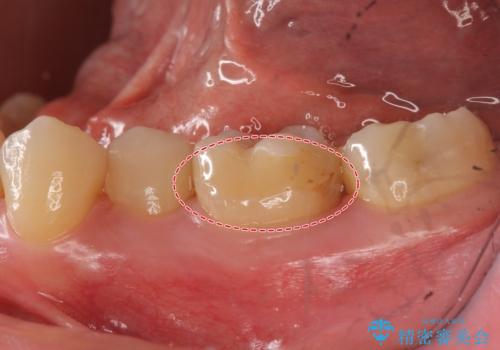

- 右下の奥歯に入れた銀歯を白くしたいとのことで来院されました。

根っこの治療がされていますが、症状もなくレントゲン画像で病変も確認できないため根管内には触れず被せ物のやり替えのみとなりました。

- 右下6 仮歯+セラミッククラウン 11000円+110000円費用は治療当時の料金となります